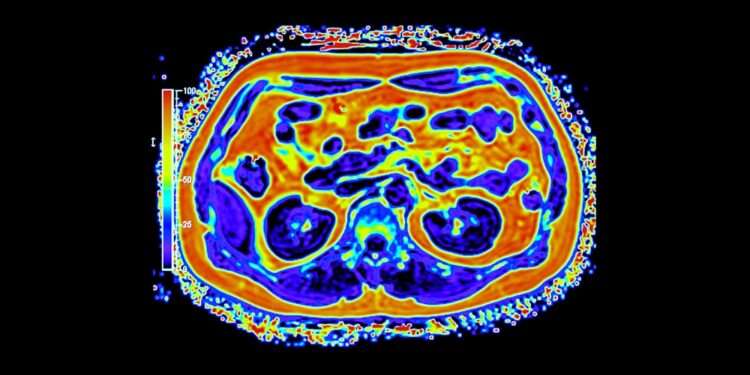

• Radiologiniai tyrimai: kompiuterinė tomografija (KT), magnetinio rezonanso tomografija (MRT), pozitronų emisijos tomografija (PET), rentgenograma,